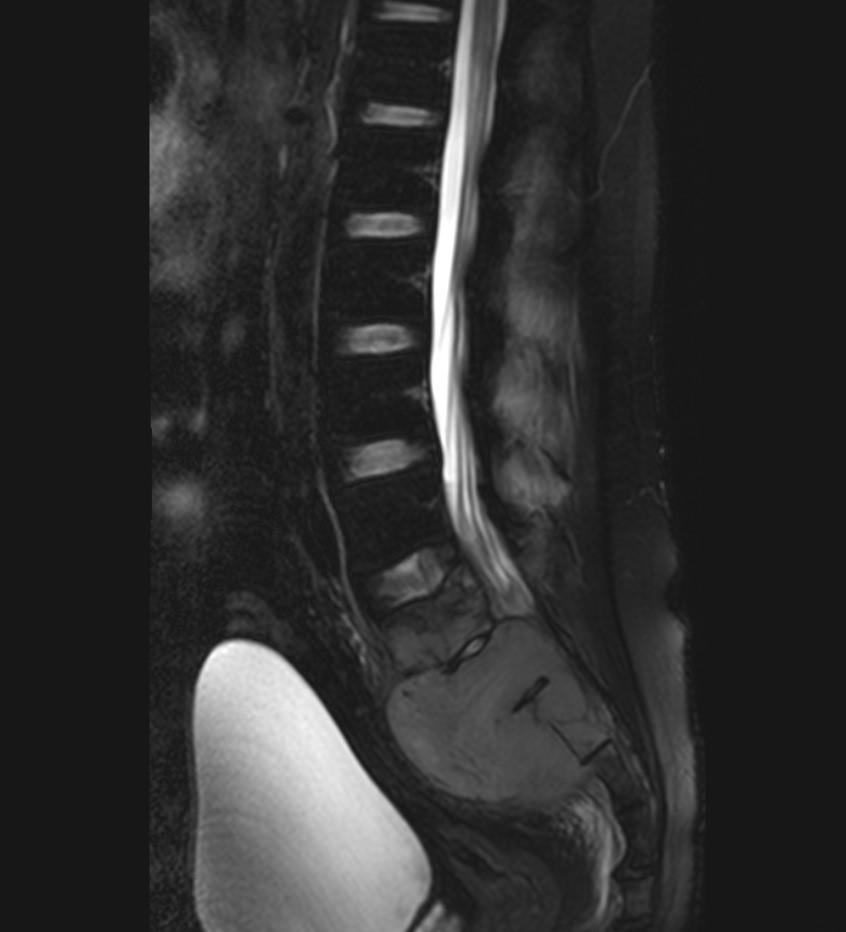

Primary lymphoma of the sacral bone is a rare myeloproliferative disease, occurring mostly after 4th decade of life and mainly in male patients. We reported a case of sacral bone lymphoma in a 24-year-old man with low back pain and radiculopathy. Imaging showed a sacral bone lesion which later proved to be non-Hodgkin’s lymphoma on histopathologic study. Lymphoma of the sacral bone is chemoresponsive and carries a good prognosis. Sacral bone lymphoma should be considered as a differential diagnosis in patients with low back pain who is not responding to analgesic treatment.